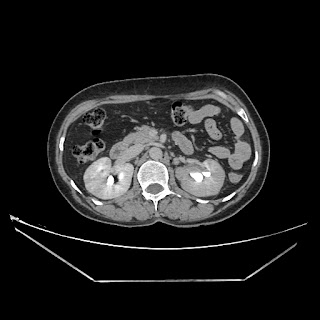

Urography images

A 50 years old woman with suffering from left sided PUJ obstruction